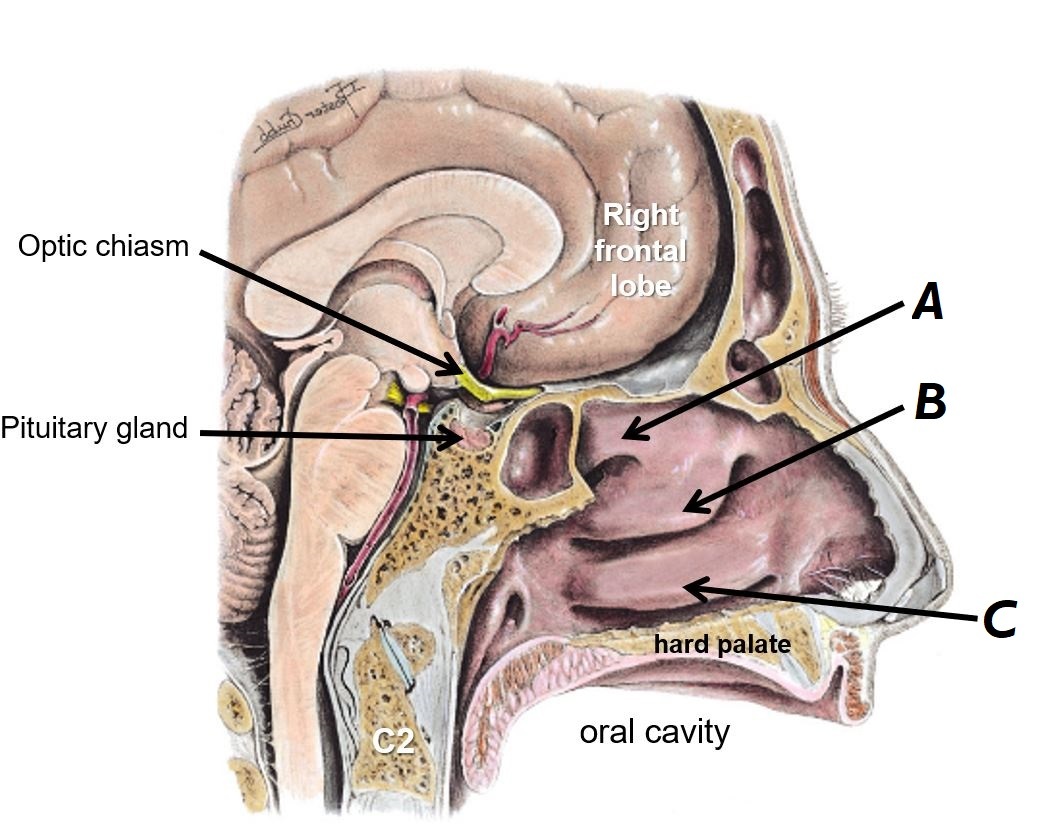

Name structures A and B

A - Optic chiasm

B - Pituitary gland

Name bones A, B and C

A - Superior nasal concha

B - Middle nasal concha

C - Inferior nasal concha